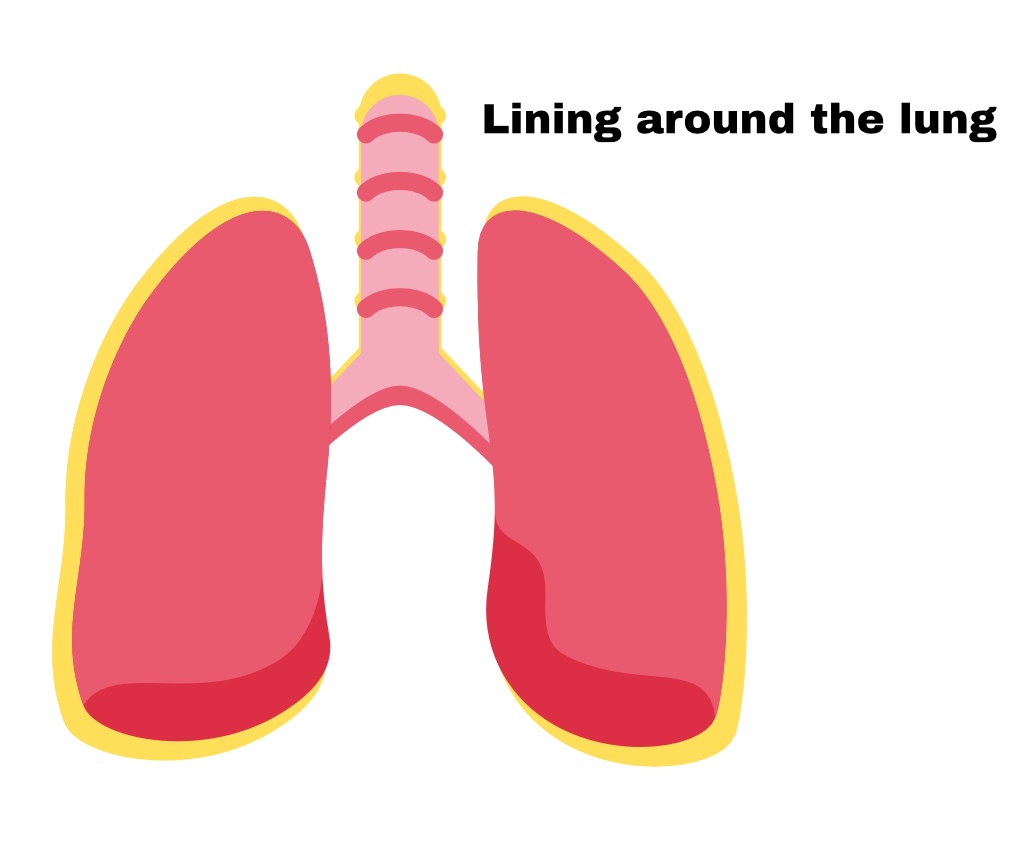

The Lungs=

Pleura

Pleura

membrane around lungs

Partial pleura

Outer layer

Visceral pleura

Deep layer (surface of organ)